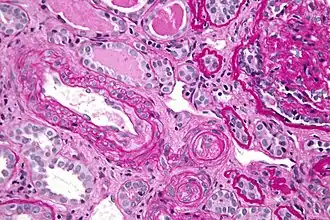

- Kidneys

Kidney involvement, in scleroderma, is considered a poor prognostic factor and frequently a cause of death.[14]

The most important clinical complication of scleroderma involving the kidney is scleroderma renal crisis (SRC), the symptoms of which are malignant hypertension (high blood pressure with evidence of acute organ damage), hyperreninemia (high renin levels), azotemia (kidney failure with accumulation of waste products in the blood), and microangiopathic hemolytic anemia (destruction of red blood cells).[15] Apart from the high blood pressure, hematuria (blood in the urine) and proteinuria (protein loss in the urine) may be indicative of SRC.[16]

In the past, SRC was almost uniformly fatal.[17] While outcomes have improved significantly with the use of ACE inhibitors,[18][19] the prognosis is often guarded, as a significant number of patients are refractory to treatment and develop kidney failure. About 7–9% of all diffuse cutaneous scleroderma patients develop renal crisis at some point in the course of their disease.[20][21] Patients who have rapid skin involvement have the highest risk of renal complications.[22] It is most common in diffuse cutaneous scleroderma, and is often associated with antibodies against RNA polymerase (in 59% of cases). Many proceed to dialysis, although this can be stopped within three years in about a third of cases. Higher age and (paradoxically) a lower blood pressure at presentation make dialysis more likely to be needed.[23]

Treatments for SRC include ACE inhibitors. Prophylactic use of ACE inhibitors is currently not recommended, as recent data suggest a poorer prognosis in patient treated with these drugs prior to the development of renal crisis.[24] Transplanted kidneys are known to be affected by scleroderma, and patients with early-onset renal disease (within one year of the scleroderma diagnosis) are thought to have the highest risk for recurrence.[25]

Scleroderma renal crisis (SRC) is a life-threatening complication of systemic sclerosis that may be the initial manifestation of the disease. Renal vascular injury (due in part to collagen deposition) leads to renal ischemia, which results in activation of the renin-angiotensin-aldosterone system (RAAS). This raises blood pressure and further damages the renal vasculature, causing a vicious cycle of worsening hypertension and renal dysfunction (e.g., elevated creatinine, edema). Hypertensive emergency with end-organ dysfunction (e.g., encephalopathy, retinal hemorrhage) is common. Thrombocytopenia and microangiopathic hemolytic anemia can be seen. Urinalysis is usually normal but may show mild proteinuria, as in this patient; casts are unexpected.

The mainstay of therapy for SRC includes ACE inhibitors, which reduce RAAS activity and improve renal function and blood pressure. Short-acting ACE inhibitors (typically captopril) are used because they can be rapidly uptitrated. An elevated serum creatinine level is not a contraindication for ACE inhibitors in this population, and slight elevations in creatinine are common during drug initiation.

Scleroderma renal crisis, the occurrence of acute kidney injury, and malignant hypertension (very high blood pressure with evidence of organ damage) in people with scleroderma are effectively treated with drugs from the class of the ACE inhibitors. The benefit of ACE inhibitors extends even to those who have to commence dialysis to treat their kidney disease, and may give sufficient benefit to allow the discontinuation of renal replacement therapy.[42]